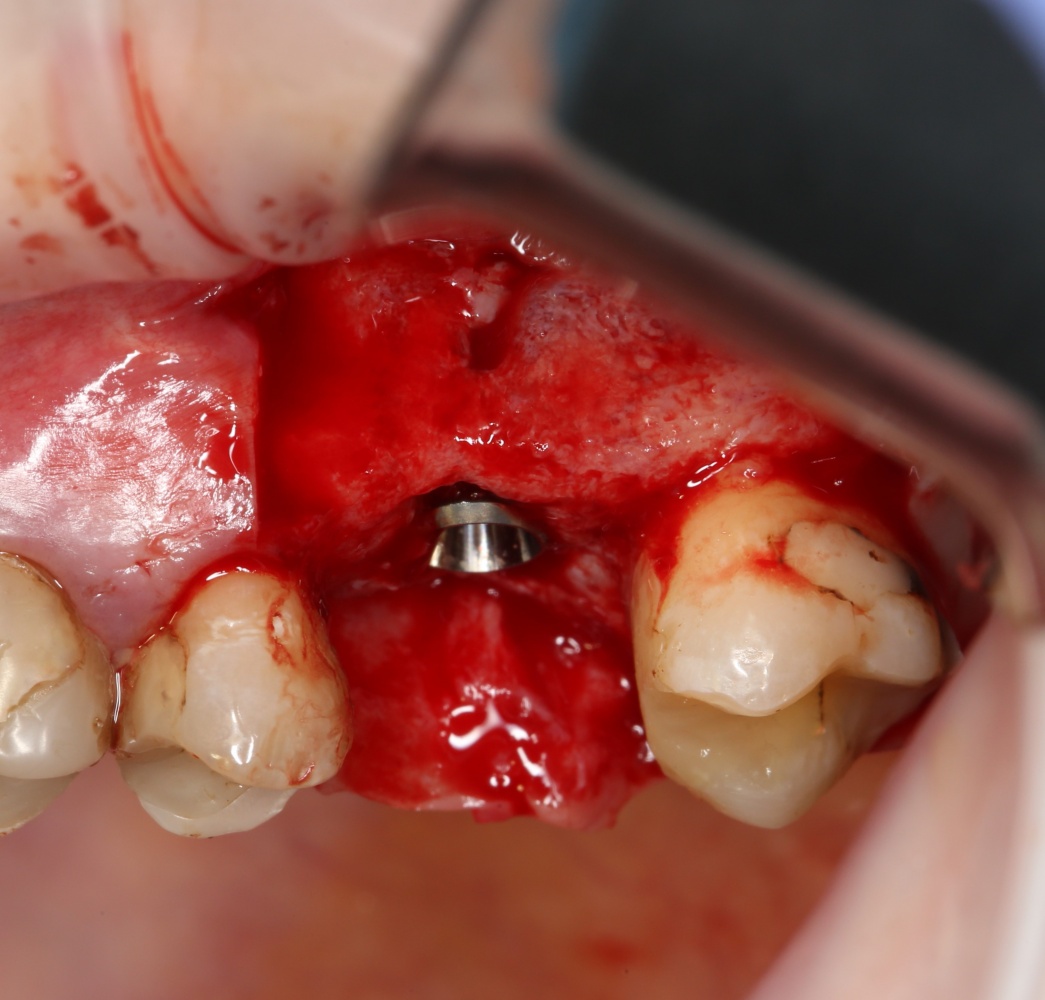

Первая операция — мы не можем сразу поставить имплантат из-за почти полного отсутствия кости между полостью рта и дном верхнечелюстной пазухи:

Через 3 месяца — вторая операция — установка имплантата в сформированный объем костной ткани: